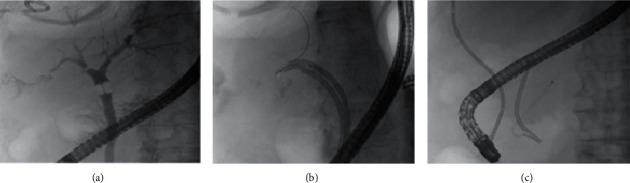

Microwave ablation is a safe and effective interventional approach, widely used in the treatment of unresectable primary or metastatic hepatic lesions. Thoracobiliary fistula is a rare postablation complication that can be treated with a conservative or surgical approach. We reviewed aetiology, pathogenesis, clinical picture, diagnostic possibilities, and therapeutic options for biliothoracic fistula developed after microwave ablation of liver metastasis. Furthermore, we reported our experience of successful conservative management of a nonhealing thoracobiliary fistula occurred after percutaneous thermal ablation of colorectal cancer liver metastasis. Our case supports a conservative approach based on percutaneous biliary system decompression and synthetic glue embolization for the treatment of combined biliopleural and biliobronchial fistula.

微波消融是一种安全有效的介入方法,广泛应用于不可切除的原发性或转移性肝病灶的治疗。胸胆瘘是一种罕见的消融后并发症,可采用保守或手术方法治疗。我们回顾了肝转移瘤微波消融术后发生胆胸瘘的病因、发病机制、临床表现、诊断方法及治疗选择。此外,我们报告了经皮热消融结直肠癌肝转移后发生的不愈合胸胆瘘成功保守治疗的经验。我们的病例支持基于经皮胆道系统减压和合成胶水栓塞的保守方法来治疗合并的胆胸膜瘘和胆支气管瘘。